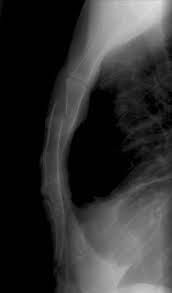

Fractured Sternum Injury Boston Chest Injury Lawyer

Fractured Sternum Injury Boston Chest Injury Lawyer from burnsjainlaw.com